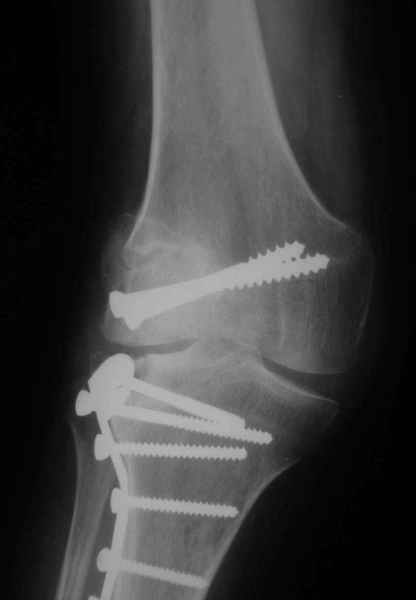

Уважаемые коллеги!На прием обратилась больная 38 лет. Травма 17.01.2005. 23.01.2005 - операция в одном из стационаров области - остеосинтез мыщелка бедра винтами, Остосинтез мыщелка большеберцовой кости L-образной пластиной.

Иммобилизация лонгетной гипсовой повязкой 2 мес. После прекращения иммобилизации, пр начале ЛФК отмечена нарастающая вальгусная деформация конечности. Рентгенограммы в приложении. Хотелось бы узнать Ваши предложения по тактике лечения

Уважаемый Евгений ! Спасибо за ответ, но мне представляется, что в нашем случае основной проблемой является не столько прогрессирующий вальгус конечности, сколько несросшийся перелом мыщелка бедра и дефект мыщелка большеберцой кости - вероятно первичная репозиция выполнялась без пластики.

Мне представляется, что прогрессирующий вальгус и обусловлен несросшимся переломом мыщелка бедра (томограммы -зона межфрагментарного склерозирования), а циклические нагрузки на сустав во время ходьбы усугубляют ситуацию. Как вы думаете, в этой ситуации насколько вероятен риск развития аваскулярного некроза мыщелка бедра?

Относительно "рубцовой подушки" я имел в виду остатки мениска ( частично вколоченного в дефект мыщелка и фрагменты хряща), все таки на рентгенограммах суставная щель в этом отделе чем то заполнена. Что касается некроза мыщелка бедра, то мне кажется он уже наступил - томограмма ноябрь5.

С учетом всего сказанного - наличия прогессирующего вальгуса конечности, довольно приличного объема движений, имеющегося, вероятно, некроза мыщелка бедра, наиболее рациональным представляется удалить пластину с б\б кости, произвести остеотомию б\б кости с коррекцией вальгуса, разгрузив тем самым наружный отдел сустава, и синтезировать фрагменты голени накостным фиксатором. Максимально тано начать восстановление движений в суставе. Скорее всего рано или поздно речь о протезировании всеже возникнет, но мы хотя бы будем иметь приличную ось конечности.